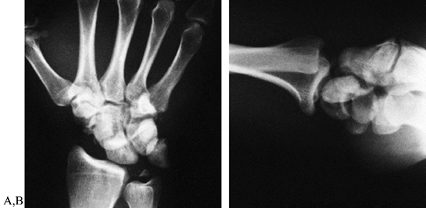

obvious clinically, resulting in a painful, tender, short, broad, and

thick wrist. On radiographs, overlap of the carpal rows, an empty-cup

lunate, and a displaced capitate

are usually obvious (Fig. 41.10 and Fig. 41.11),

Figure 41.10. PA (A) and lateral (B)

radiographs show details of a complicated transosseous perilunate type of fracture–dislocation. It can be described as a transscaphoid, transulnar styloid, perilunotriquetral dislocation with an associated subluxation of the pisiform. The lunate and triquetrum are still in a relatively normal alignment with the forearm, and all physicians would be willing to call this a perilunate type of dislocation. |

Figure 41.11. PA (A) and lateral (B)

radiographs of the same wrist show the lunate displaced palmarward and ulnarward, permitting the distal carpal row elements, particularly the capitate and hamate, to intrude toward the radius, displacing the scaphoid into flexion and the triquetrum ulnarward. Most physicians would call this a lunate dislocation because the carpal bones, other than the lunate, are fairly well aligned with the forearm. Nevertheless, the lunate is still in contact with a portion of its articular surface with the radius and still has intact ligament connections by its palmar radiolunate ligaments; therefore it is a stage of perilunate dislocation. |